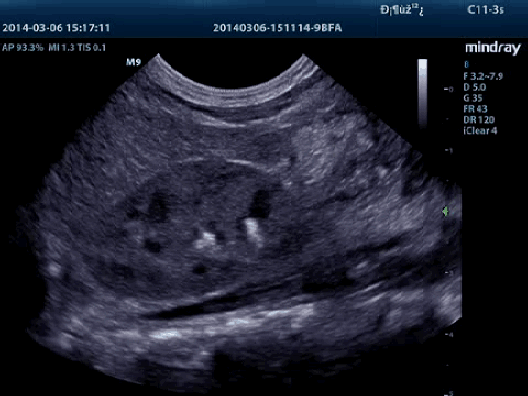

Визуализация с применением контрастных веществ UWN+ (нелинейная визуализация в ультрашироком диапазоне)

Самое большое преимущество УЗ-сканера M9T заключается в поддержке запатентованной Mindray технологии, позволяющей расширить возможности визуализации с применением контраста. Технология UWN+ дает возможность M9T обнаруживать и использовать как вторичные гармоники, так и нелинейные первичные сигналы, создавая изображения более высокого качества.

- Более высокая чувствительность к второстепенным сигналам, меньший расход действующего вещества

- Более длительное время действия активного вещества и более низкие требования к интервалу измерения

- PSHI™ (гармоническая визуализация с фазовым сдвигом)

Изолированная гармоническая визуализация для улучшения контрастного разрешения, обеспечивающая более четкое изображение с превосходным пространственным разрешением и меньшим уровнем шума.